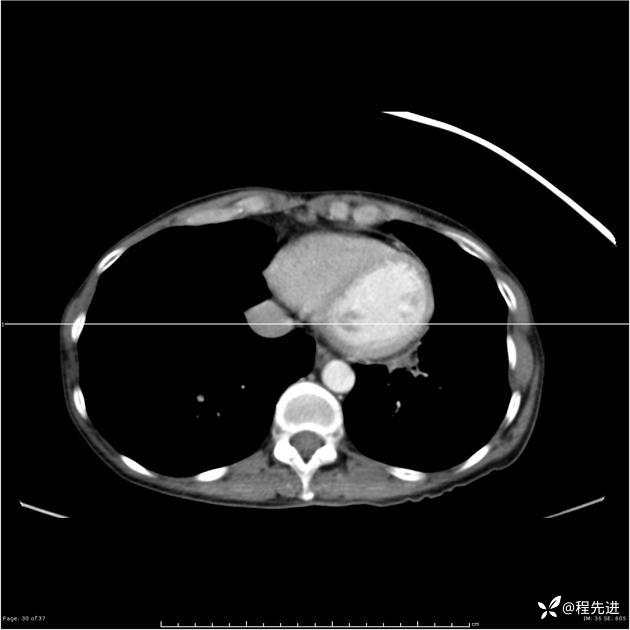

病例女,53岁,气管、左主支气管、下叶支气管内结节,乳头状瘤?期待你的精彩解读

女,53岁

乳头状瘤?